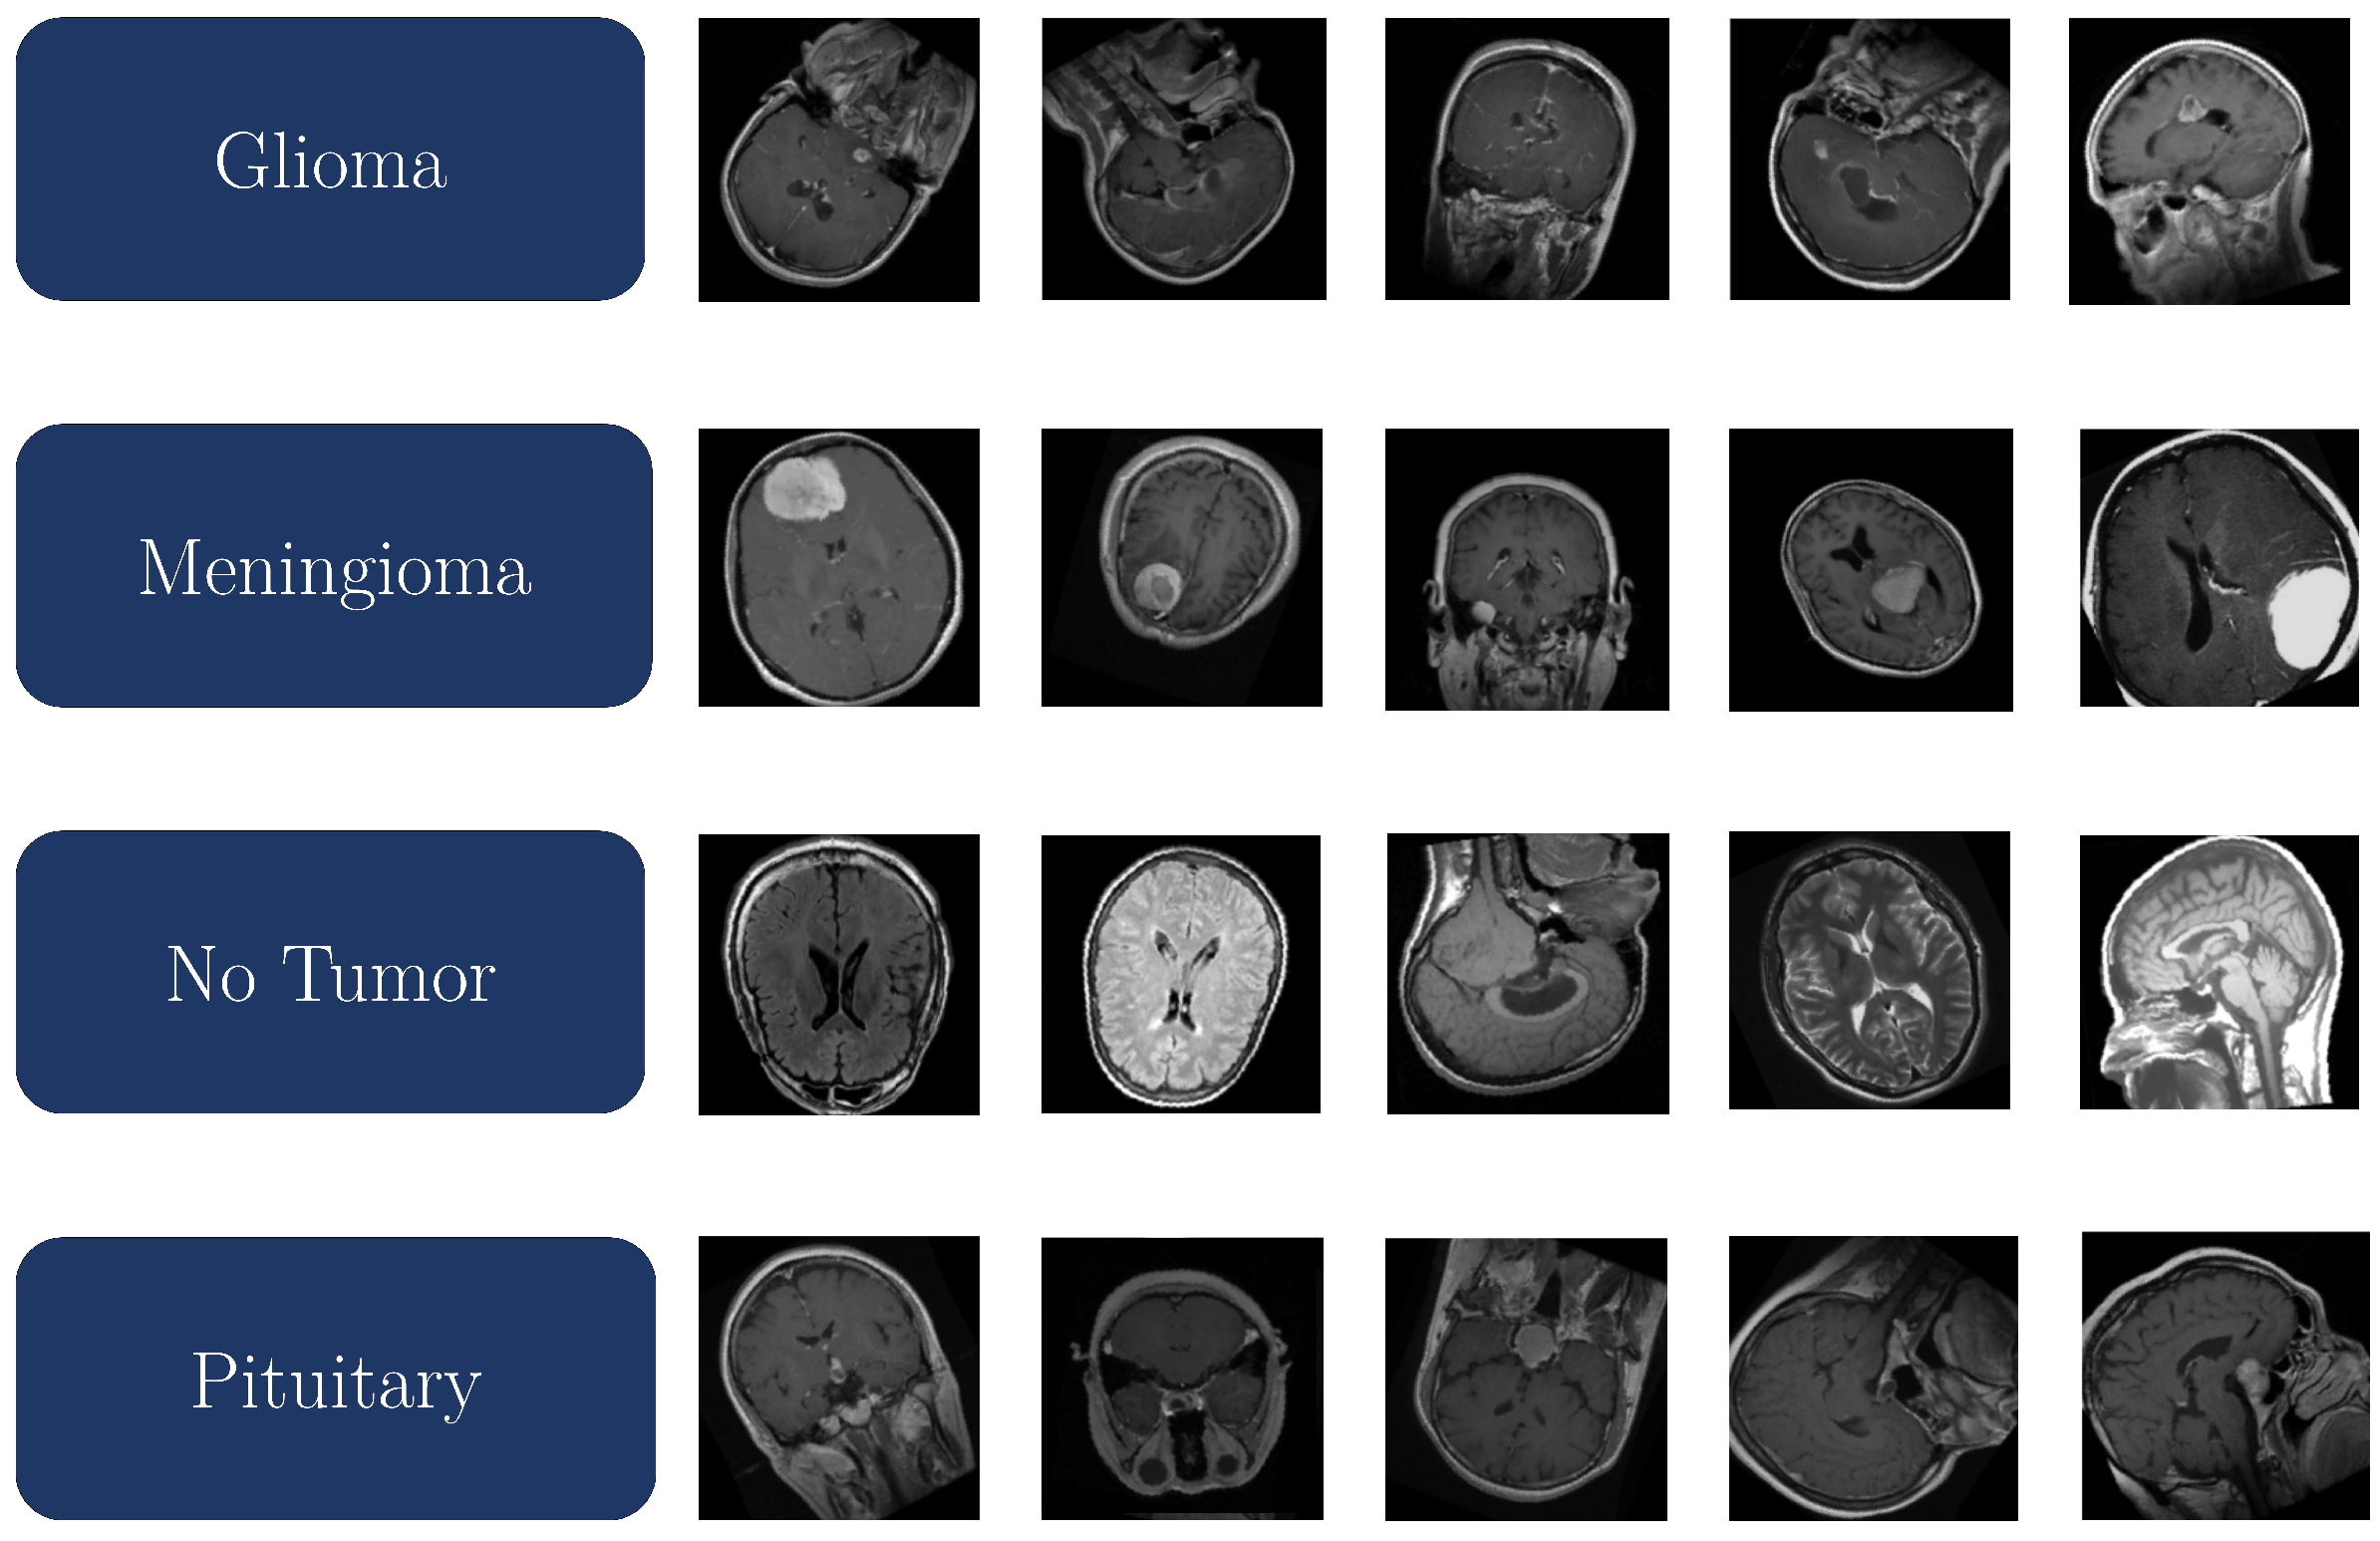

The Msoud MRI dataset [48] from Kaggle is constructed from three publicly available datasets: Figshare, Sartaj, and Br35H. It has a total of 7023 grayscale magnetic resonance images in JPEG format, including coronal, sagittal, and axial cuts, divided into four diagnostic classes: glioma, meningioma, no tumor, and pituitary tumor. This dataset was employed for training, validation, and testing of various TL-based models implemented in this study. The training subset comprises 1321 glioma, 1339 meningioma, 1595 no-tumor, and 1457 pituitary tumor images, totaling 5712 images. The testing subset consists of 300 glioma, 306 meningioma, 405 no-tumor, and 300 pituitary tumor images, totaling 1311 images. The class-wise distribution is shown in Table 1. The dataset’s diversity in anatomical presentation and tumor morphology enhances its suitability for developing and validating robust DL models for brain tumor classification. According to Table 1, the dataset was explicitly divided into 5712 images for training (81.33%) and 1311 images for testing (18.67%). These partitions were predefined by the dataset’s original authors and were respected in our implementation to ensure consistency with existing literature. Importantly, regarding the validation, we further applied a stratified 5-fold cross-validation strategy within the training subset, ensuring class balance across folds and preventing any overlap of images between folds. Although the dataset does not include patient-level identifiers, all experiments were conducted at the slice level as provided by the source. Each model was evaluated using a test dataset completely isolated from the training and validation processes, ensuring strict independence between training and testing phases. The use of stratified cross-validation and fixed test partition helps ensure the robustness and reproducibility of the reported results.

Figure 3 presents a representative sample of the Msoud dataset, illustrating the visual characteristics and grayscale intensity distribution typical of the MRI scans used for model training and evaluation.